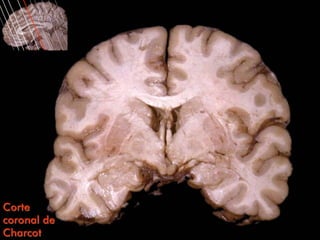

Corte

coronal de

Charcot

Surco del cíngulo                     Circunvolución frontal superior

Circunvolución

frontal media

Surco

Circunvolución                                                                                    central

del cíngulo

Cuerpo calloso                                                                                    Cápsula

interna

Septum

pellucidum

Lámina

medular

Cuerpo del                                                                                        externa

ventrículo lateral

Putamen

Globo

pálido

lateral

coronal de                                   Cuerpo mamilar             Globo         Lámina

Charcot              Cuerpo del fórnix                        Tálamo    pálido medial medular interna

Surco del cíngulo Circunvolución frontal superior Circunvolución frontal media Surco Circunvolución central del cíngulo Cuerpo calloso Cápsula interna Septum pellucidum Lámina medular Cuerpo del externa ventrículo lateral Putamen Globo pálido lateral Corte coronal de Cuerpo mamilar Globo Lámina Charcot Cuerpo del fórnix Tálamo pálido medial medular interna